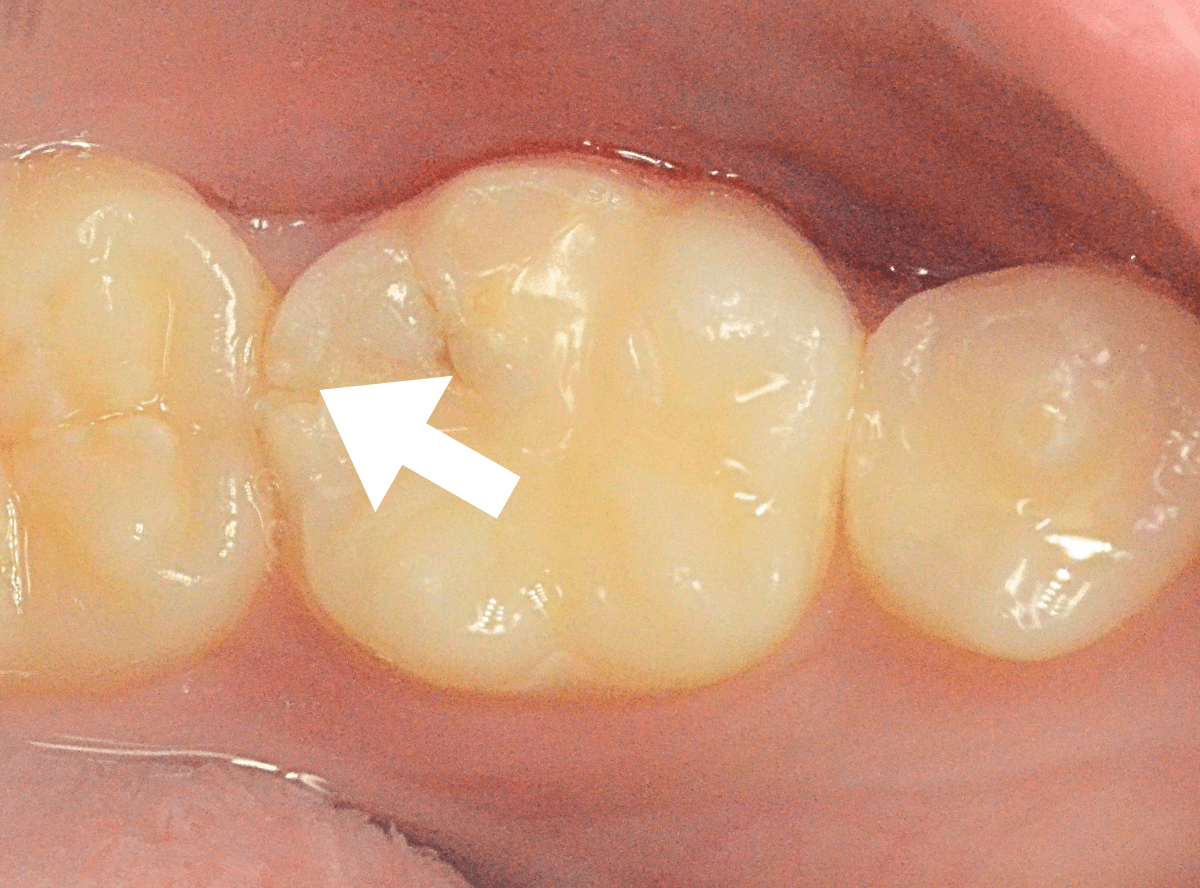

Case.25 深い虫歯の治療~無事にセラミック・インレーへ

今回は、上の奥歯が深くて広い虫歯になっていた方のケースです。

〇部が虫歯の部分です。

この写真からは深い虫歯があるのは想像つきません。

レントゲン写真で確認します。

青い線が神経、赤い線が虫歯の部分です。

前後の歯とも、かなり深く広い虫歯になっているのがわかります。